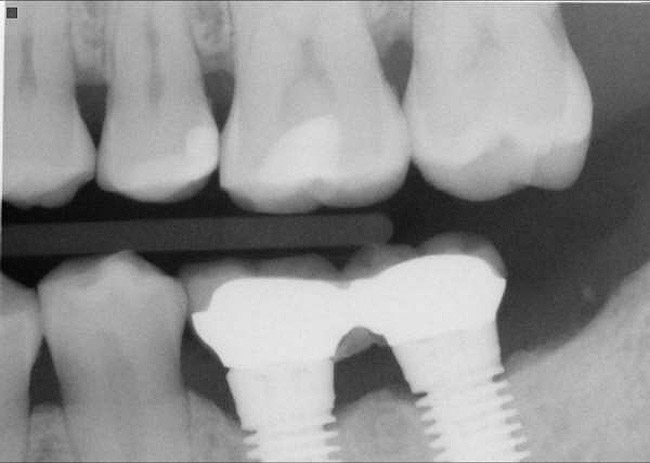

The horizontal aspect of implant spacing is critical to avoid bone loss on adjacent teeth or implants. Single-tooth implants should be placed 1.5 mm to 2 mm from the adjacent teeth,19,20 and implants should have at least 3 mm of space between them21 (Figure 12). By keeping a minimum 1.5-mm distance from the adjacent tooth and a minimum distance of 3 mm between adjacent implants, angular defects resulting from crestal bone remodeling can be kept from becoming horizontal defects19-22 (Figure 13). This distance allows the bone on the adjacent tooth to stay at its current level. Conversely, if bone loss on the adjacent tooth or implant occurs, the bone loss will not affect the adjacent tooth or implant. This is especially critical in the anterior regions of the mouth where papilla height is more important for an esthetic result.23-27

Figure 13  Radiograph depicting the necessity of horizontal placement parameters to prevent vertical defects from becoming horizontal defects.

Figure 13